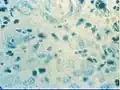

Le terme clinique correct pour désigner la donovanose est granulome inguinal[2]. Le granulome est une réaction inflammatoire de type nodulaire, et le mot inguinal fait référence à la région inguinale, qui est le siège de cette infection. La maladie est communément connue sous le nom de donovanose, d’après les corps de Donovan, qui sont un signe diagnostic. Découvertes par Charles Donovan[5], ces inclusions intracellulaires représentent des bactéries qui ont été absorbées par des cellules immunitaires nettoyeuses, les phagocytes mononucléés ou histiocytes.

Les antécédents sexuels du patient sont recherchés. Pour les médecins expérimentés, le diagnostic est clinique à la simple vue des ulcères. Toutefois, il peut être nécessaire pour le soignant de prélever un fragment de tissu afin d’effectuer un diagnostic de certitude de la maladie. La coloration de Wright-Giemsa permet de faciliter la lecture anatomopathologique du prélèvement. En outre, la présence de corps de Donovan dans les prélèvements tissulaires confirme le diagnostic de donovanose.

Donovanose lésions microscopiques

Donovanose lésions microscopiques Donovanose chez l'homme